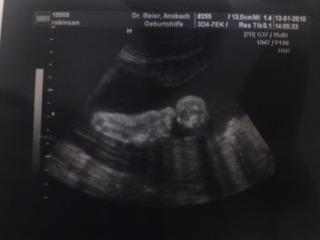

sooo gestern hatte ich VU... es is alles bestens..versorgung zwischen kind und plazenta is super! CTG war auch gut nur sie hasst es einfach! sie is dann immer wach und versucht von dem ding wegzuschwimmen.. immer suess wie man das rauschen hoert.. nun zur kleinen maus... sie hat sich von BEL wieder in die Querlage gelegt.. *schrei* aber wir haben ja noch zeit.. ihre beine sind in ihrem gesicht also konnte man unten wieder alles gut sehen und diesmal konnte sogar ICH erkennen das es ein maedchen wird ;) doc meine aber das die kleine groesser ist als normal.. *angst bekomm* nicht das die normale geburt jetzt noch an der groesse scheitert.. sie wiegt jetzt knapp 1800 gramm groesse weiss ich leider nicht.. hab ein so suesses US bildchen bekommen.. ihr erster fussabdruck! naechster termin is am 26.1.

Bild zu VU gestern! - Forum für März - Mamis

och sieht das bild niedlich aus *hihi* schön das alles okay is 1800 gramm? also ich hab in der ss woche schon gelesen die hatten über 2000 ;) oh du auch querlage, dann hippeln wir wohl gemeinsam :D aber auf jedenfall freut es mich das alles In Ordnung ist! lg

Hallöchen !!! Schön das alles okay ist , und schön das DU es endlich auch richtig erkennen konntest das es ein Mädel ist, ich kenne das ja grins Schade das du nicht die Grösse weisst , hätte mich mal interessiert ... Uiiiiiii der erste Fussabdruck wie süüüüüss Ich denke sie ist noch am hin oder her überlegen ob sie nun BEL lieben will oder SL grins... haha Freut mich jedenfalls das alles zum besten ist ... LG Jessi